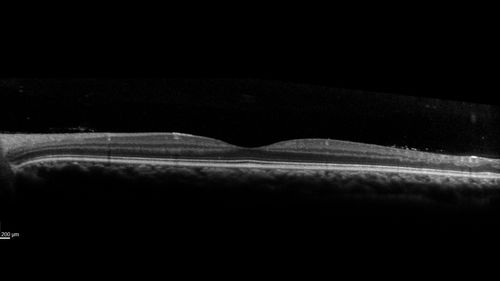

Eales Disease and fresh vitreous hemorrhage - 20 year old man

20 year old mane with fresh vitreous hemorrhage in the right eye.  At age 15 he had a PPV and laser in the left eye and laser in the right eye.  The vision is OD 20/80 PH 20/25, OS 20/25.  The left eye has a mild cataract.  He had prior testing for coagulopathies which was negative.  Testing done for syphillis and TB was negative.  Additional laser was done to prevent further bleeding in the right eye.